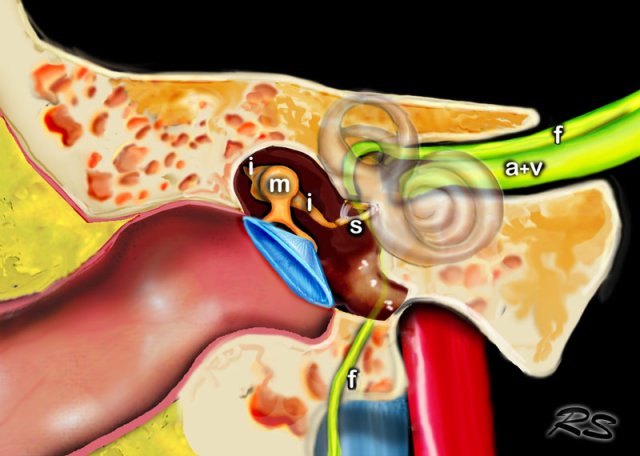

The middle ear consists of the tympanic cavity and the antrum.

The tympanic cavity is the major portion of the middle ear and contains the ossicles.

The tympanic membrane, the malleus, incus and stapes transfer soundwaves to the stapes footplate, which is attached to the base of the cochlea in the oval window.

Ossicles

In many illustrations you will see the incus connecting medially to the malleus, but this is not correct.

On the coronal reconstruction on the left it is clearly demonstated that the incus is positioned posterolaterally to the malleolar head.

The long crus of the incus subsequently runs inferomedially to the stapes.